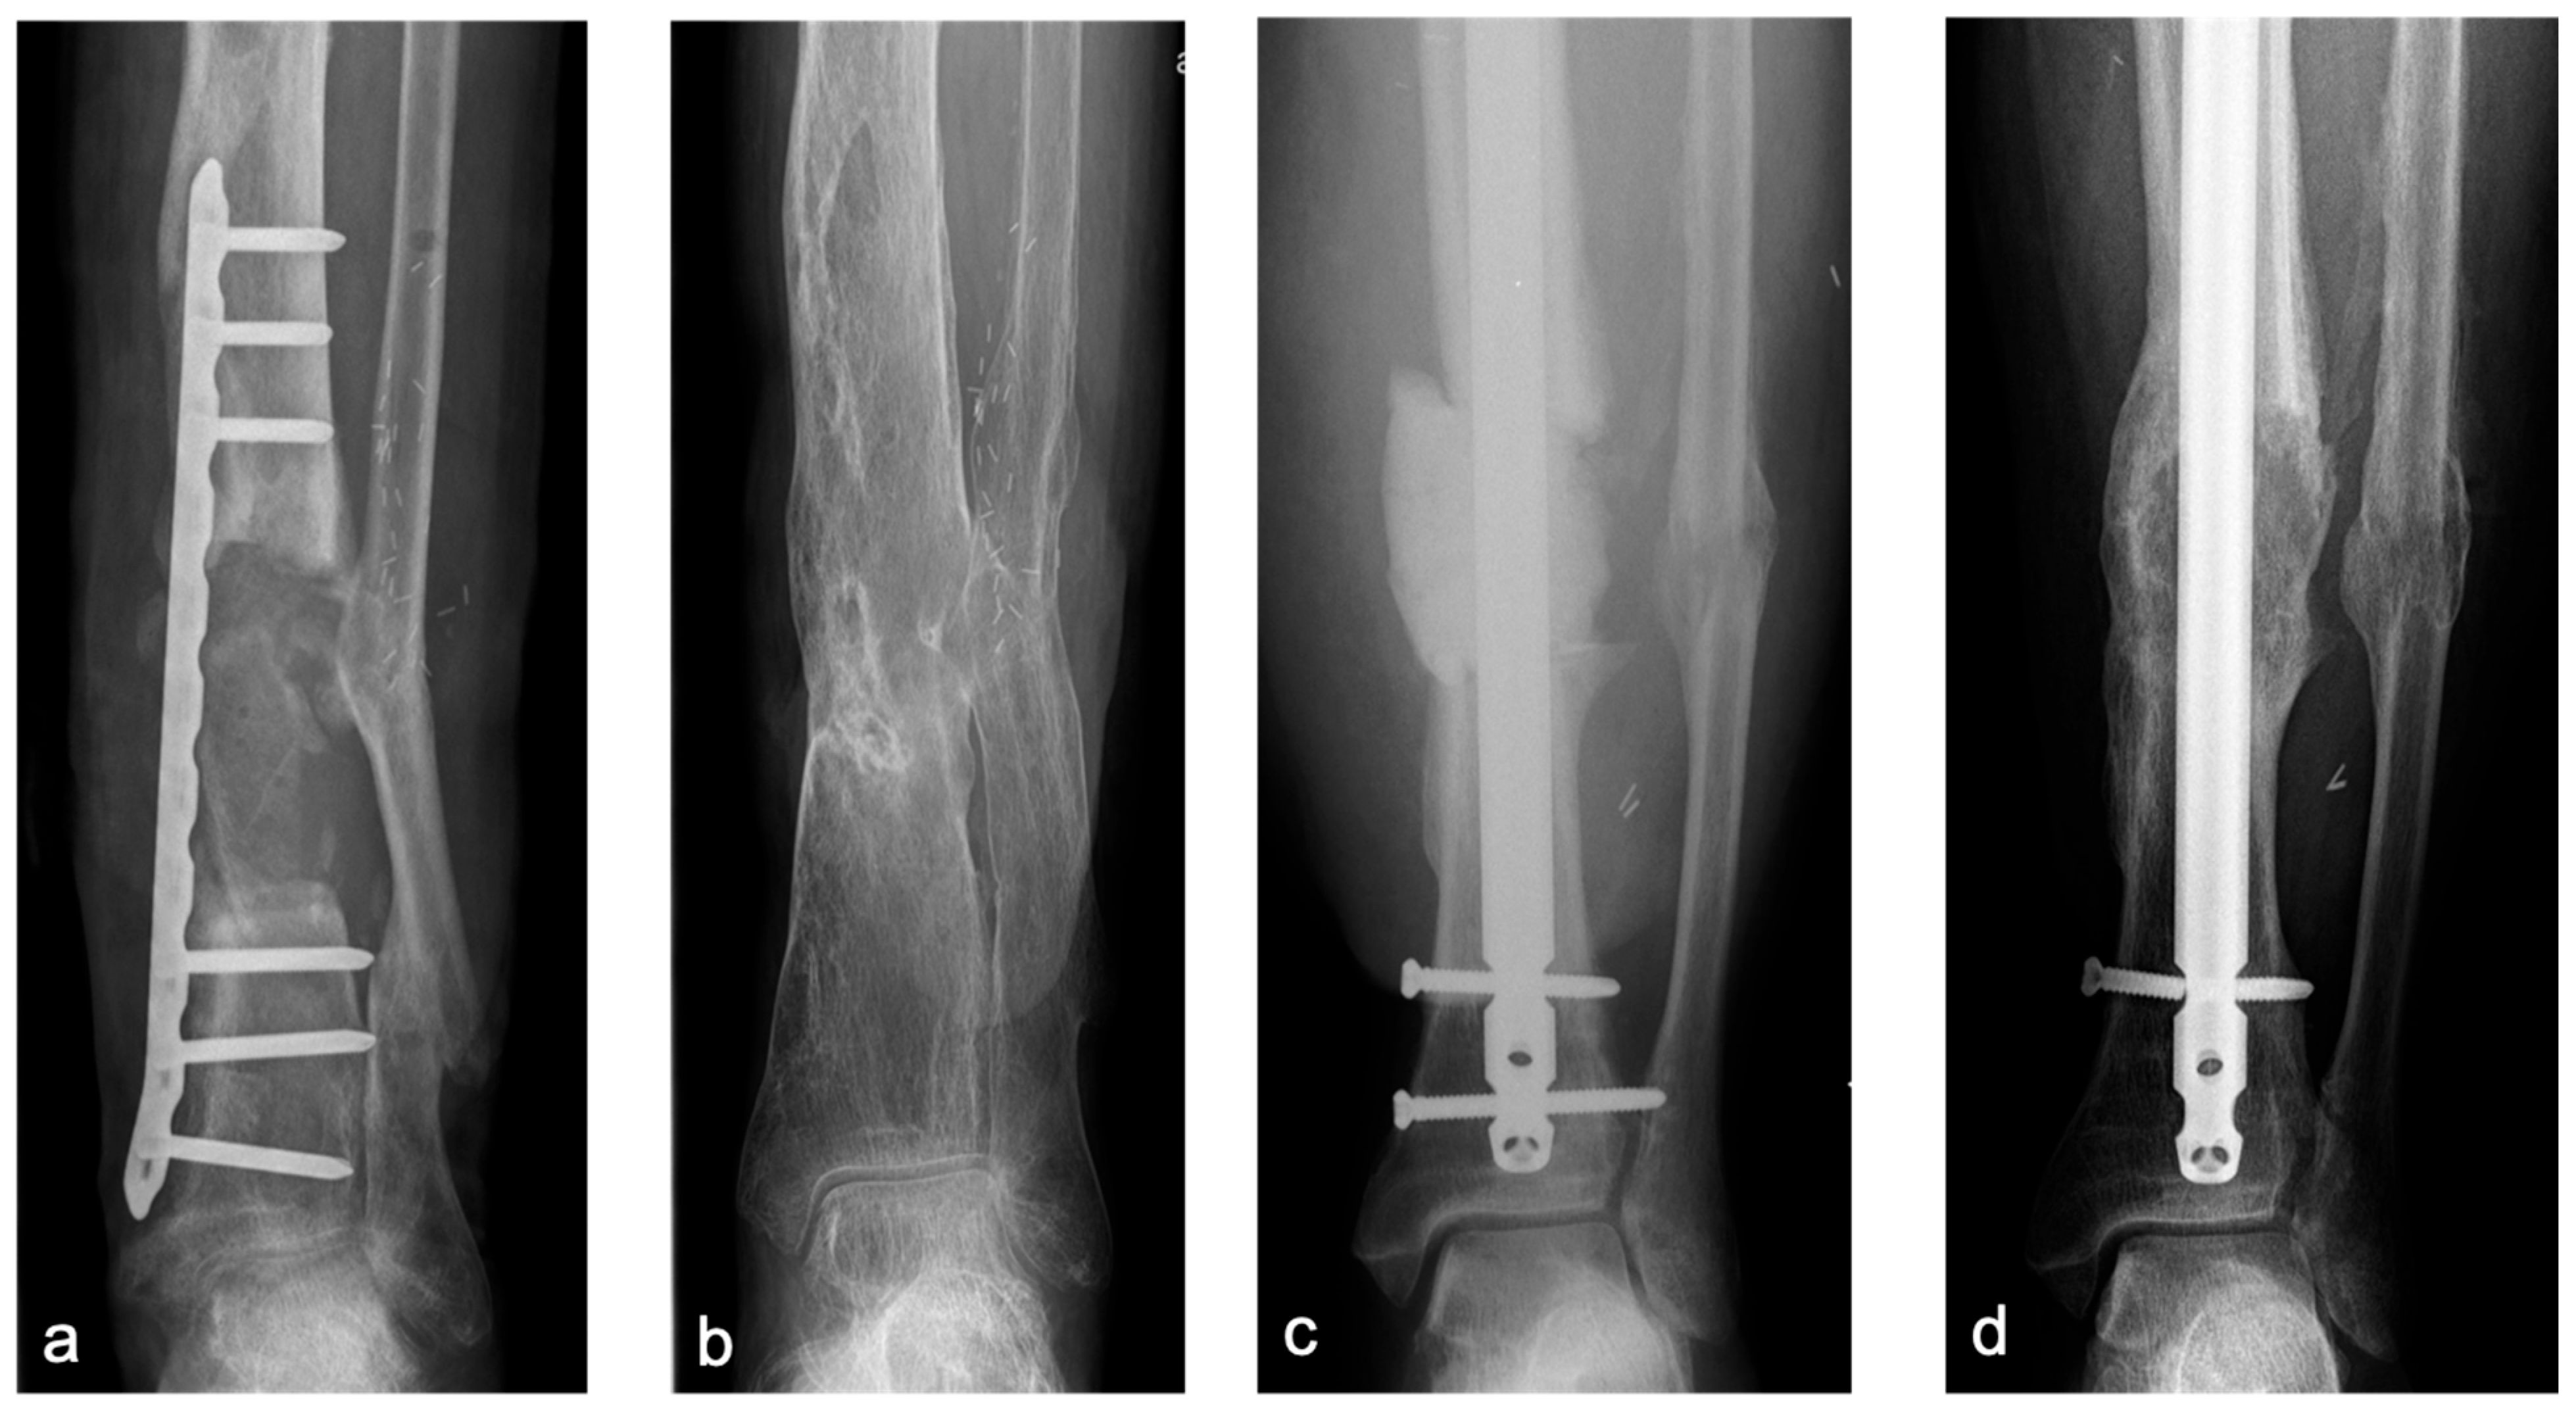

| locking plate n = 32 (65.3%) intramedullary nail n = 15 (30.7%) external fixation (Ilizarov) n = 1 (2%) cast n = 1 (2%) | n = 20 (40.8%) | 42.08 ± 2.19 mm (21.3–83.9) | one graft n = 27 (55.1%) two grafts n = 21 (42.9%) three grafts n = 1 (2%) | bicortical n = 10 (20.4%) tricortical n = 39 (79.6%) | anterior n = 47 posterior n = 1 anterior + posterior n = 1 | single n = 23 (46.9%) parallel n = 22 (44.9%) In line n = 4 (8.2%) | Press-fit n = 35 (71.4%) cerclage wire n = 2 (4.1%) screws n = 12 (24.5%) | n = 17 (34.7%) |